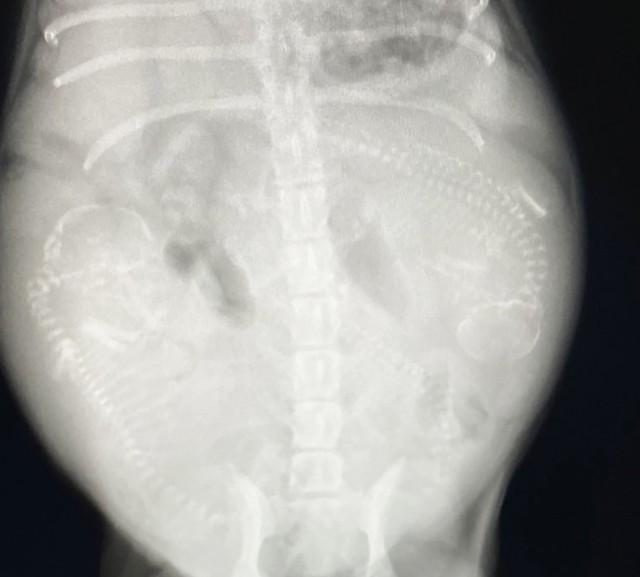

さっそく動物病院へと連れて行き検査してもらうと、結果はトリマーさんの直感通りの妊娠中。

エコーにはモゴモゴと動く赤ちゃんに様子が映し出されていて、さらに「2~3週間後には産まれます」という診断でした。